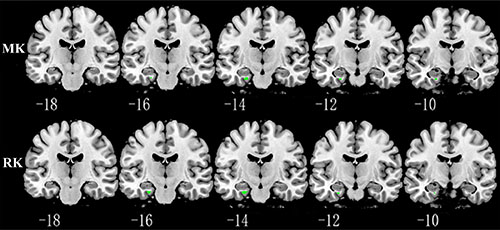

Relative to TT homozygotes, KIBRA C-allele carriers showed increased AxD, MD, RD in right postcentral gyrus and right insula, decreased AK, MK in right postcentral gyrus, as well as decreased FA (fractional anisotropy), KFA in right caudate head (Figure 2). The results are listed in Table 3. Moreover, KIBRA C-allele carriers showed increased MK and RK in the left parahippocampus, compared to TT homozygotes (Figure 3). The results are listed in Table 4.

Figure 3: Representative coronal images show increased MK and RK in parahippocampus (p < 0.001, with a minimum cluster size 10) in KIBRA C-allele carriers compared with TT carriers. Abbreviation: MK: mean kurtosis; RK: radial kurtosis.

Another interesting finding was that KIBRA C allele carriers showed greater MK and RK in the left parahippocampus than TT homozygotes. In contrast to conventional DTI parameters, MK and RK are regarded as indices of the complexity of tissue microstructure, reflecting the density, orientation, and degree of organization of cell membranes, axon sheaths, and myelin layers [20, 45–47]. Using diffusion kurtosis imaging with a cohort the included individuals with AD or mild cognitive impairment (MCI) and normal controls, Gong et al. recently reported significantly decreased hippocampal MK in MCI and AD, which reflects the loss of microstructural compartments such as neuronal cell bodies, axons, synapses, and dendrites. In addition, using resting fMRI, Filippini et al. [48] detected greater default mode network synchronization involving medial temporal and medial-prefrontal cortical areas in APOE ε4-carriers than noncarriers. Our results are, to some extent, consistent with these studies. Increased MK and RK in the left parahippocampus in healthy young KIBRA C allele carriers likely reflects a compensatory mechanism to maintain relatively normal memory function.